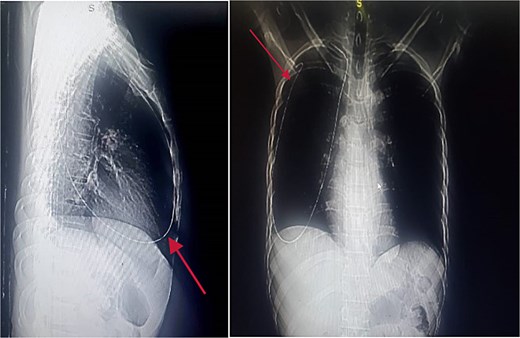

Chest and abdominal X-rays revealed the guide wire extending from the right subclavian vein through the superior vena cava (SVC), right atrium, and inferior vena cava (IVC) to the proximal right femoral vein (Figs 5 and 6).

Chest X-ray showing guide wire extending from the right subclavian vein to the SVC and via the right atrium to the IVC.